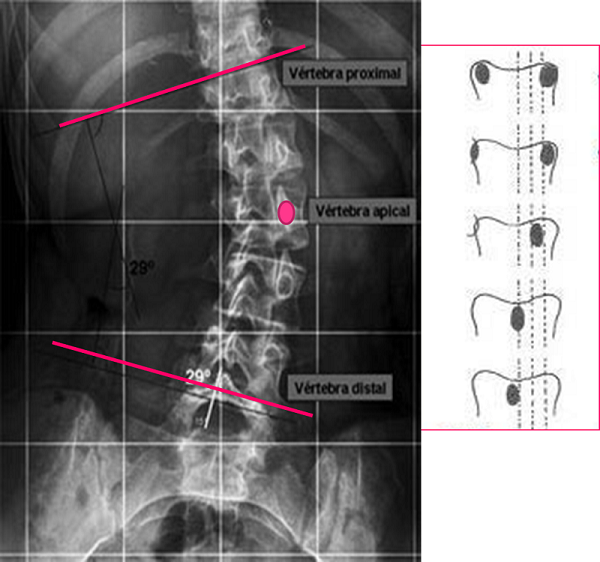

Cada curva se define entre dos vertebras, al inicio y al final de esta. Son las “vértebras límite”, las cuales se identifican como aquellas a partir de las cuales la curva cambia de dirección y, por ende, tienen la mayor inclinación hacia el lado cóncavo de la escoliosis. Se eligen de tal manera que entre ellas formen el mayor ángulo posible y corresponden a aquellas con la superficie del platillo vertebral más inclinado hacia la concavidad (Figura 9).

Figura 9. Angulo de Cobb e índice de Moe de la escoliosis. El ángulo de Cobb se determina entre las dos vértebras que están más inclinadas hacia la concavidad, límites a su vez de la curva escoliótica. El índice de Moe valora la imagen asimétrica de los pedículos y da información de la importancia de la rotación de la vértebra ápex. Mostrar/ocultar

Existen distintas formas de medir el ángulo de esta curva, pero el más frecuente es el ángulo de Cobb. Este ángulo está definido entre dos líneas que pasan, una de ellas paralela por el platillo superior en la vértebra límite superior y la otra por el platillo inferior de la vértebra límite inferior.

Normalmente en el centro de la curva se localiza la vertebra ápex (aunque a veces el ápex de la curva es un disco intervertebral). Corresponde al punto con mayor desplazamiento lateral desde eje central de la columna. Es la vértebra más deformada, la que está más rotada. En esta vértebra se mide el índice de Moe que determina la situación, más o menos centrada, de los dos pedículos (Figura 9). Cuanto más en el ápex y cuanto más rotada, el índice de Moe es mayor porque la vértebra proyecta los pedículos en posición asimétrica. Las apófisis espinosas también se deforman apuntando a la concavidad.